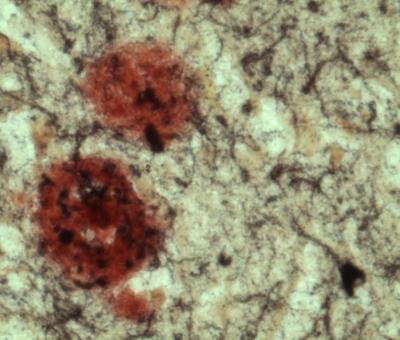

LA JOLLA, Calif., August 20, 2012 – The underlying causes of Alzheimer's disease are not fully understood, but a good deal of evidence points to the accumulation of β-amyloid, a protein that's toxic to nerve cells. β-amyloid is formed by the activity of several enzymes, including one called BACE1. Most Alzheimer's disease patients have elevated levels of BACE1, which in turn leads to more brain-damaging β-amyloid protein. In a paper published August 15 in The Journal of Neuroscience , researchers at Sanford-Burnham Medical Research Institute (Sanford-Burnham) found that BACE1 does more than just help produce β-amyloid—it also regulates another cellular process that contributes to memory loss. This means that just inhibiting BACE1's enzymatic activity as a means to prevent or treat Alzheimer's disease isn't enough—researchers will have to prevent cells from making it at all.